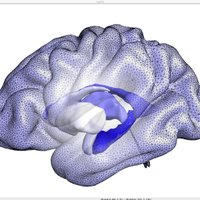

Deformation of a brain template to reconstruct the gray matter of a person's brain from an MRI scan. The video shows the integration of the ODE with the Euler method, learned by V2C-Flow. Code: github.com/ai-med/Vox2Cor… Article: authors.elsevier.com/c/1iVAd4rfPmHq… wonga et al TU München